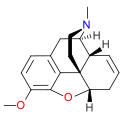

Structures

| Morphides | ||||

|---|---|---|---|---|

Codeine Codeine |

Morphine Morphine |

Oripavine Oripavine |

Pseudomorphine Pseudomorphine |

Thebaine Thebaine |